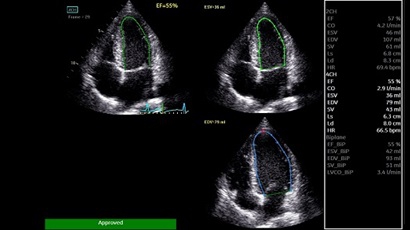

AUTO 2D EF:

Да

AFI:

• AUTO 2D EF - режим автоматической недопплеровской количественной оценки глобальной сократительной функции ЛЖ (по Simpson).

• AFI - режим цифровой недопплеровской качественной и количественной оценки региональной сократительной функции ЛЖ.